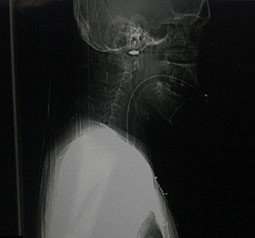

Rolanda Gedminas adlı turist olaya şahit olanların müdahaleleri ile hemen hastahaneye götürüldü. Suratında 19.2 santimlik bir delik oluşturan ok ile birlikte hemen ameliyata alınan turist uzun süren bir operasyon sonucunda başarıyla suratındaki oktan kurtuldu. Doktorların yaptığı açıklamada suratına saplanan ok 1-2 milimetre daha içeri saplansaydı olay yerinde hayatını kaybedebileceğini açıkladılar. Litvanyalı turist önlem için yoğun bakıma alınırken kendisine ok ile saldırı gerçekleştiren Rod Woollis polisin derin araştırması sonrası Grimsby Park yakınlarındaki bir barda yakalandı. Sabıkası incelenen zanlının daha önce şiddet suçundan 3.5 yıl hapis yattığı ortaya çıktı. Oklu saldırgan cinayete teşebbüsten yargılanmak üzere cezaevine gönderildi.